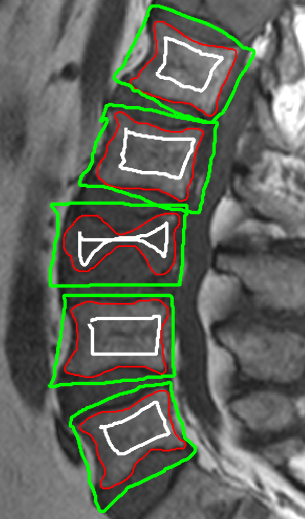

Comparing our proposed BGrowth (BG) to GrowCut (GC), in general, BG keeps similar recall and achieves better precision, consequently, a higher F-measure. Figure 6 shows the segmentation results for BGrowth, GrowCut and LazySnapping in a case with three benign VCFs in L1, L3 and L5 (L2 and L4 are normal). Note that, the dark and bright regions within the same vertebral bodies difficult the segmentation for all methods, presenting spiked borders due to the neighbours structure intensities, which are very similar (dark). On these cases, even the manual segmentation is challenging and requires much experience of the human operator.

BG generated smother and more delineated borders, which are closer the ground-truth. The LS also produced promising results. However, sometimes it fails to delimit borders when the interior annotation is closer to the ground-truth and the exterior annotation is not, as shown in results for L4 in Figure 6.

![]() |

| (a) GT and Annotations | (b) BGrowth (BG) | (c) GrowCut (GC) | (d) LazySnapping (LS) |